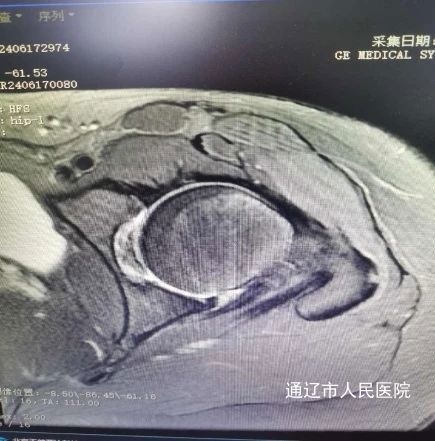

术前影像:

患者张某,女性,24岁,2年前开始出现左侧髋关节肿痛伴活动受限,严重影响日常生活,门诊经过查体及髋关节半髋磁共振检查诊断为:髋臼撞击综合征合并盂唇撕裂。由于患者年纪较轻,左侧髋关节撞击导致髋臼盂唇损伤,长期疼痛,胡中申主任医师带领其关节外科团队对该病例进行详细周全地讨论,综合评估患者病情并得到家属同意后,建议实施髋关节镜手术治疗。